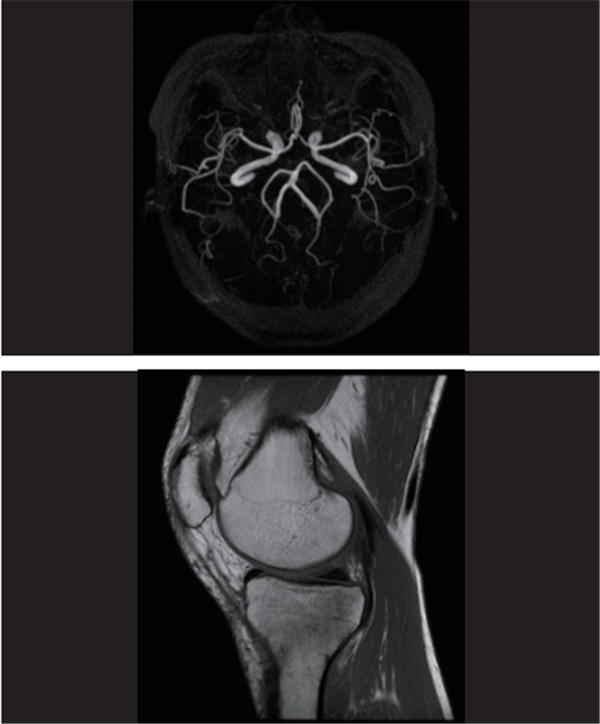

1.5T高场磁共振图像展示

(头颅MRA成像、膝关节平扫)